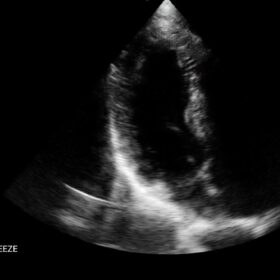

Cardio 2D, Color and PW doppler